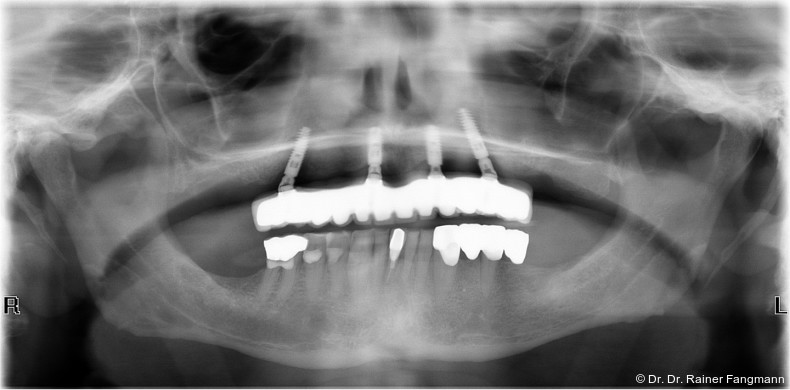

Die Fragestellung zur Implantatanzahl im Oberkiefer oder Unterkiefer ist oft sehr patienten- und behandlerspezifisch zu betrach-ten. Für Kostenträger ist die Frage oft von übergeordneter Relevanz. Für den Praktiker stellt sich die Frage nach der Umsetzbarkeit. Zudem sind auch das Knochenangebot und dessen Qualität für die Anzahl der Implantate und auch der Implantattypus maßgebend. Folgender Beitrag zeigt ein Fallbeispiel mit drei Implantaten, sechs Jahre in situ.

Ein immer viel diskutiertes Thema ist die Implantatanzahl beim All-on-X-Konzept. Diese ist von vielen Faktoren abhängig. Zu nennen sind der Implantattyp, der Implantatdurchmesser und die Implantatinnengeometrie. Im Weiteren sind die Knochenqualität und -quantität zu betrachten. Auch spielt die Gegenbezahnung zum All-on-X-Kiefer eine entscheidende Rolle, sodass hier keine einheitliche Linie für den Oberkiefer erkennbar ist. Es gelten in der Regel vier bis sechs Implantate als ausreichend. Im Unterkiefer sind es in der Regel vier. Wie dargestellt, reichen bei diesem Implantatsystem auch drei Implantate aus.